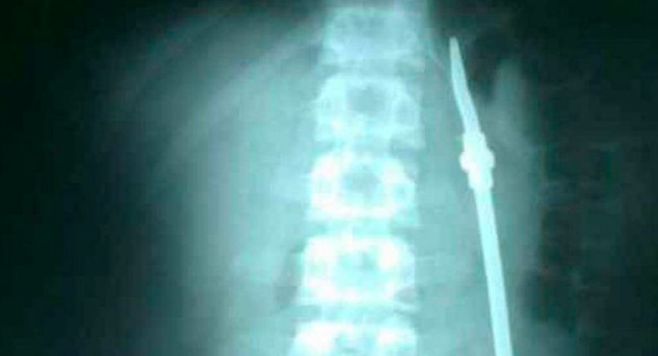

Con una extraña excusa, un preso se tragó una bombilla y, cuando terminó la operación para su extracción, se fugó del hospital San Martín en Paraná.

Se trata de Carlos Gabriel Olivares, quien cumple condena en la Unidad Penal N°1 de esa capital, quien explicó que había absorbido el elemento porque tenía problemas familiares. Producto de la urgencia, debió ser internado e intervenido quirúrgicamente.